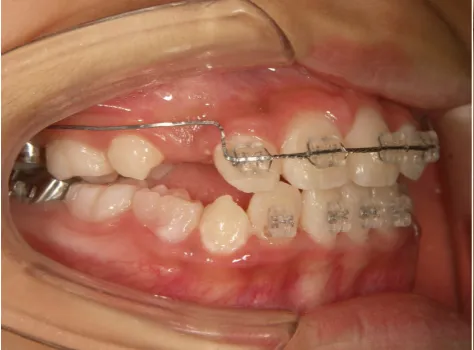

治療中➁小3:9y8m QH、BH、前歯並び替え終了

モノブロック装置(筋機能的咬合誘導装置)スタート